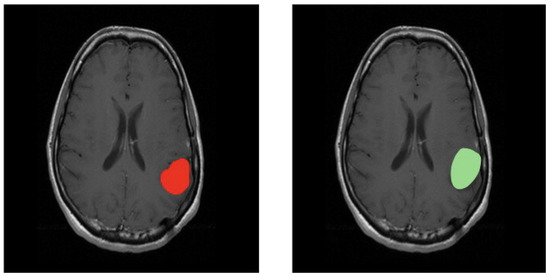

3.3. Third Scenario